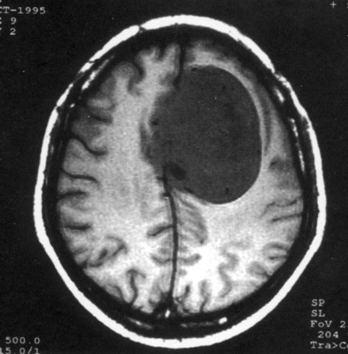

问题 病历摘要:??患者女性,37岁。大便时突起炸裂样头痛3小时,伴喷射样呕吐。既往体健。体检:T37.5℃,BP145/90mmHg,R20次/分,P85次/分。神志清楚,颅神经检查无异常,颈强直,克、布氏征(-),四肢肌力、肌张力正常,病理征(-)。 应首先采取哪些处理措施?提示:CT示右额叶直回处小血肿、蛛网膜下腔出血。